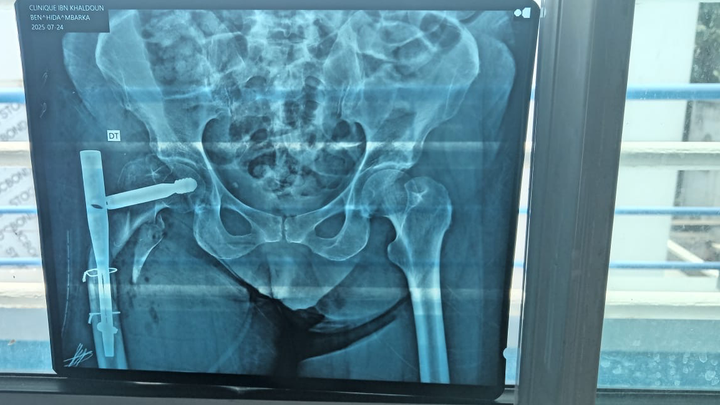

Je m’appelle Imane je vis à Montréal. Ma maman risque l’amputation après un grave accident le 22 juillet au Maroc.

Six opérations ont échoué. Seule une clinique spécialisée peut sauver sa jambe — mais nous n’avons pas les moyens.

My name is Imane living in Montreal. My mom is fighting to keep her leg after a terrible car accident on July 22nd in Morocco.

Six surgeries failed. Doctors say only a specialized clinic can save her from amputation — but it’s far beyond our means.